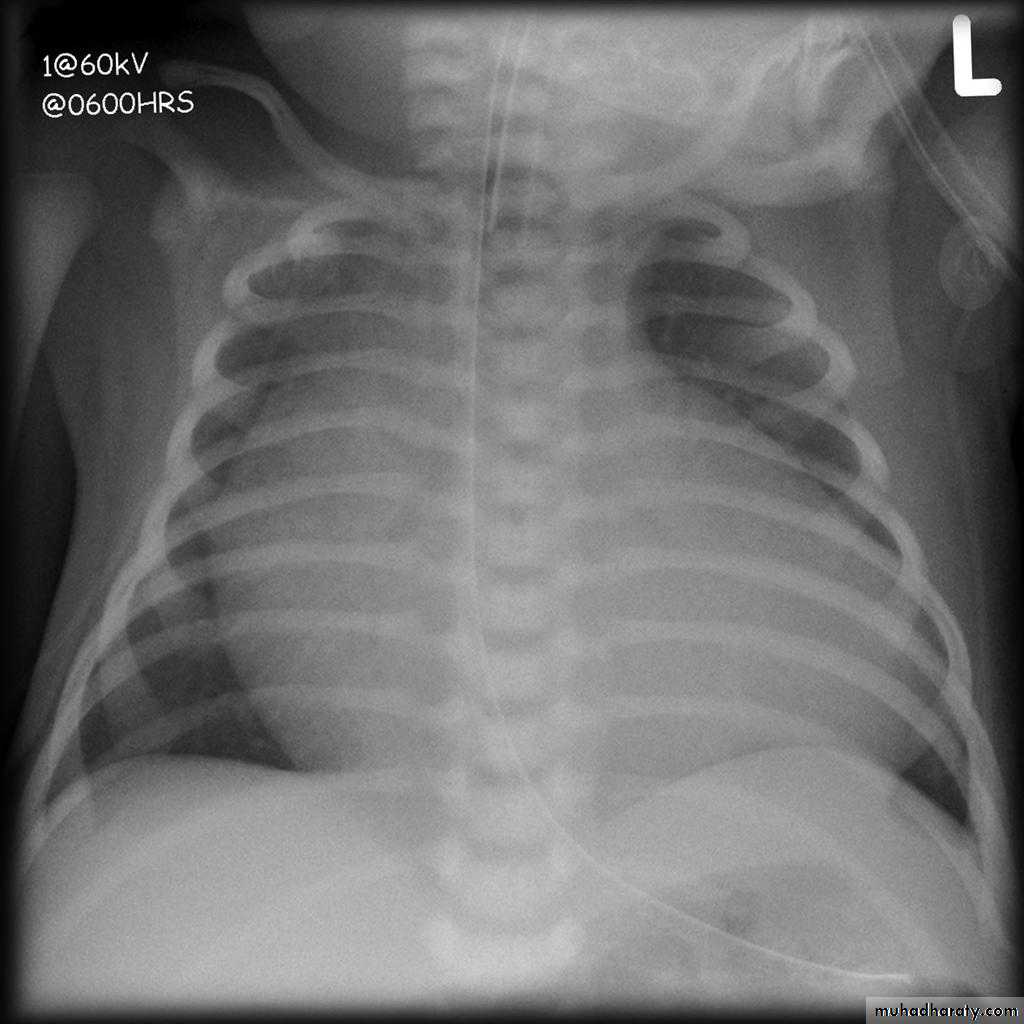

23.normal neonatal chest XR ( normal thymus gland )

24. normal chest XR of the infant( normal thymus gland)